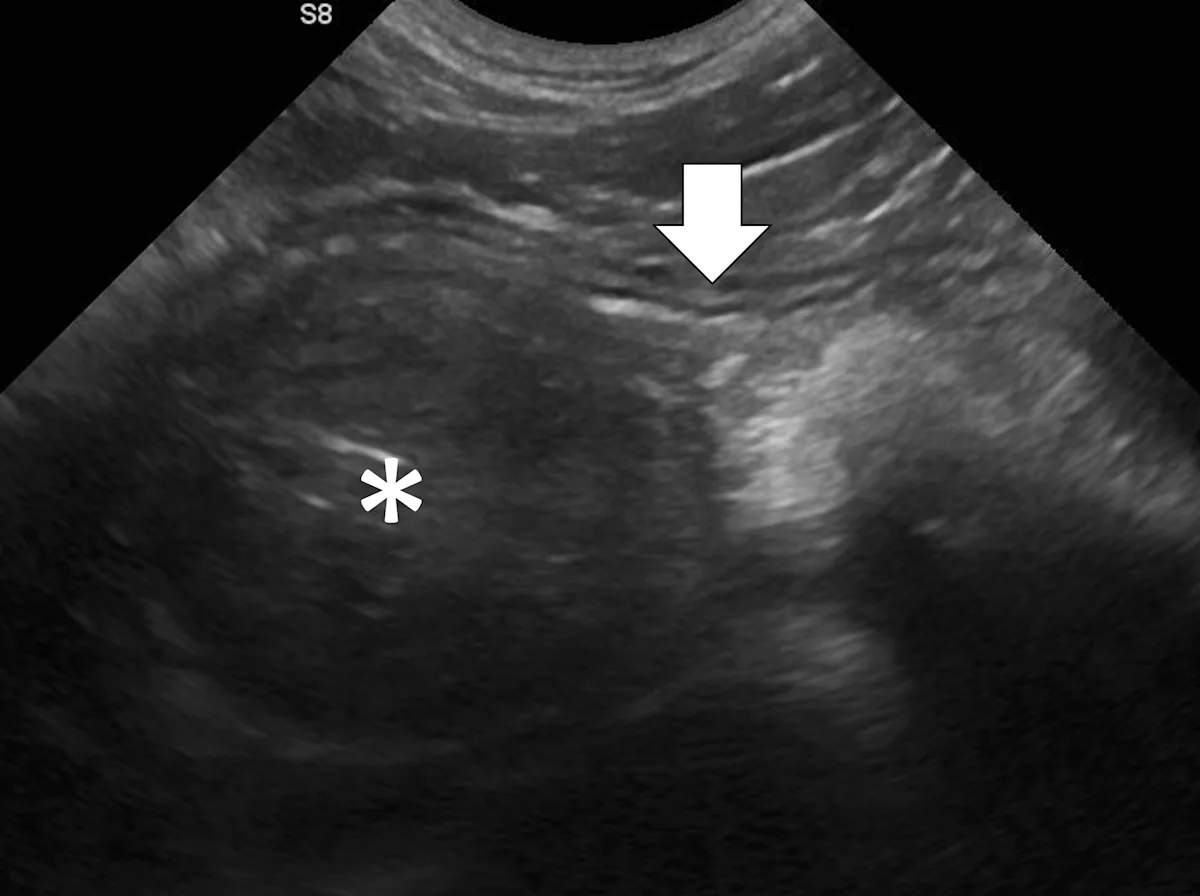

Linear foreign body obstructions occur when an object (eg, string, cloth) becomes stuck orally but extends aborally through the intestinal tract. Peristaltic contractions typically cause the small intestine to travel orally, eventually bunching. As a result, ultrasonographic findings include intestinal bunching (ie, plication) with or without a hyperechoic linear structure coursing through the lumen of the affected bowel (Figure 4).9-12 In some cases, trapped gas can cause a line that can be mistaken for the linear foreign body. Plication should not be confused with normal peristalsis or corrugation (Figure 5). With corrugation, the serosal margin is normal, and the mucosa and submucosa are undulant; with plication, the serosal margin is affected.14 In chronic cases, the mesentery surrounding the affected bowel may become hyperechoic, which can help identify the site of obstruction. Sterile inflammation and transudation may then result in focal accumulation of a small volume of free fluid. Mesenteric changes and peritoneal effusion also increase concern for bowel rupture and septic peritonitis. Patients may have concurrent findings of pyloric outflow or small intestinal mechanical obstruction, depending on the size and nature of the ingested cloth or string.

Abdominal ultrasound of an 11-month-old neutered male domestic shorthair cat with a surgically confirmed toy ball connected to a linear foreign body anchored in the pylorus (asterisk). The proximal duodenum is plicated (black arrows) with a hyperechoic linear structure (white arrows) coursing through the center. Normal small intestine can be seen adjacent to the plicated duodenum (caret).